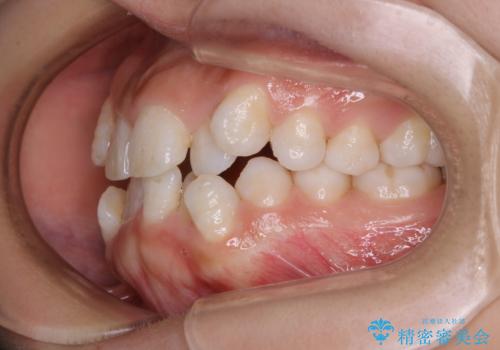

インビザライン単独での抜歯矯正治療

- 当院にてインビザライン治療を行っていた同僚の方からのご紹介でいらした方です。楽器を演奏されるとの事で、インビザラインによる矯正治療をご希望されました。治療の途中で一時的にワイヤー矯正に切り替える可能性もあることもご了承頂いた上で治療を行いました。

1日20時間以上、正しくインビザラインを使用して頂いたおかげで、ワイヤーに切り替えることなく矯正治療を終了することが出来ました。抜歯症例でしたが比較的短期間で見た目が劇的に改善し、大変喜んでいただけました。